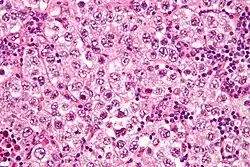

| Micrograph of a seminoma, a common germ cell tumor. | |